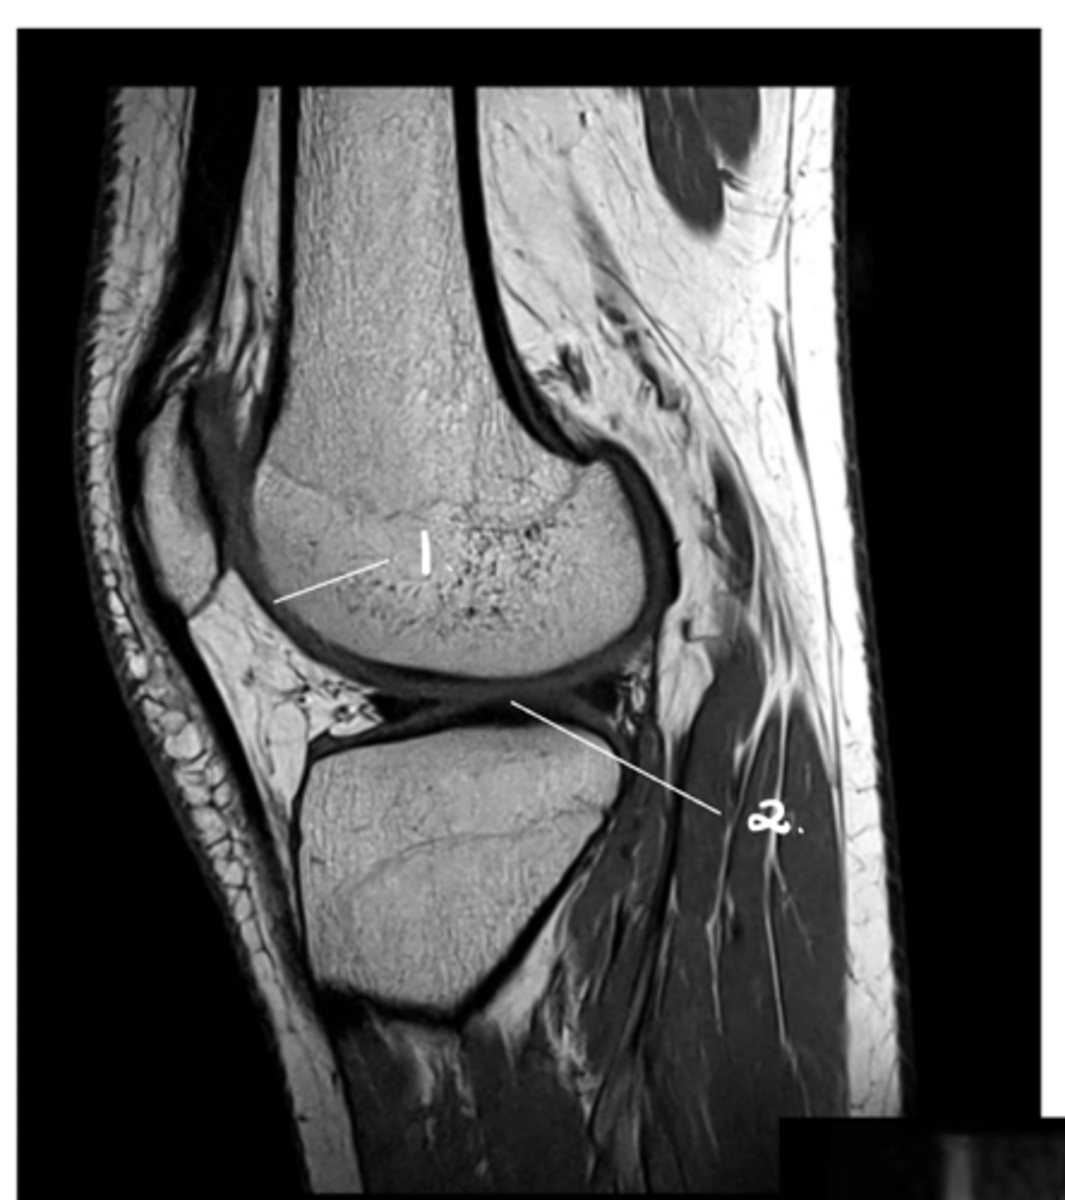

1. Hyaline cartilage (all of the grey)

2. Meniscus (looks kind of like a thickening of the cartilage from this angle)

Label 1 & 2.